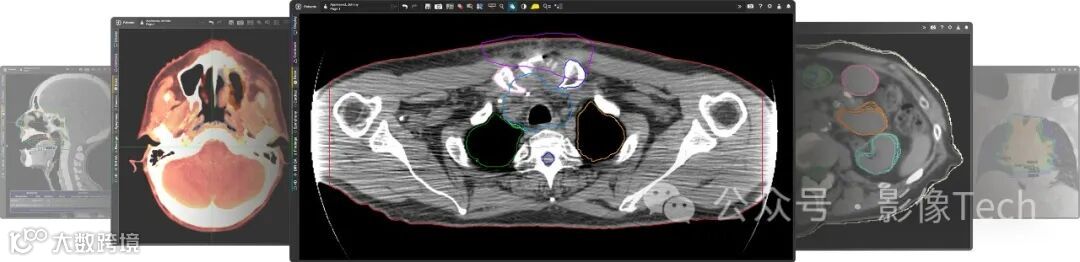

公司旨在为放射肿瘤学、核医学、放射学、介入放射学、分子、神经和心脏的成像提供创新的软件解决方案。公司到目前为止推出了MIM Maestro®、Contour ProtégéAI+™、MIM Encore®等软件。

GE医疗计划将MIM Software的解决方案整合到其先进的可视化产品中,以支持以AI技术为基础的影像分割、轮廓绘制、放射剂量测定分析等服务。这一整合旨在帮助医疗机构更好地为患者提供医学影像,同时在放射学、分子成像和放射肿瘤学等领域推动创新。